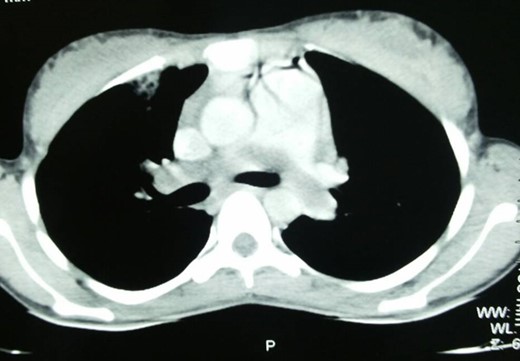

A 25-year-old lady was admitted in the pulmonology ward with the diagnosis of pneumonia. The patient had presented with a history of progressive shortness of breath, chest pain and persistent cough with occasional haemoptysis. She had a history of being treated with antibiotics and anti-TB drugs in outpatient basis. She had had spontaneous abortion 8 months back. Since her symptoms were persistent and her general condition was deteriorating, she was admitted to the ward. On examination, she had crepitations in bilateral chest and an oxygen saturation of only 80%. Chest X-ray showed bilateral infiltrations. CECT chest was done, which revealed pulmonary embolus occluding the main pulmonary artery, and right and left pulmonary arteries (Fig. 1). Venous Doppler did not reveal thrombosis of the lower limbs or IVC. Pulmonary thromboembolectomy was done and embolus (Fig. 2) was sent for histopathological examination. The examination revealed it to be metastatic choriocarcinoma (Fig. 3). Serum beta-human chorionic gonadotrophin (HCG) level was found to be significantly high. CECT pelvis and head were negative for pelvic and CNS metastases. She was managed further with chemotherapy (EMACO regimen) with excellent response to the treatment.